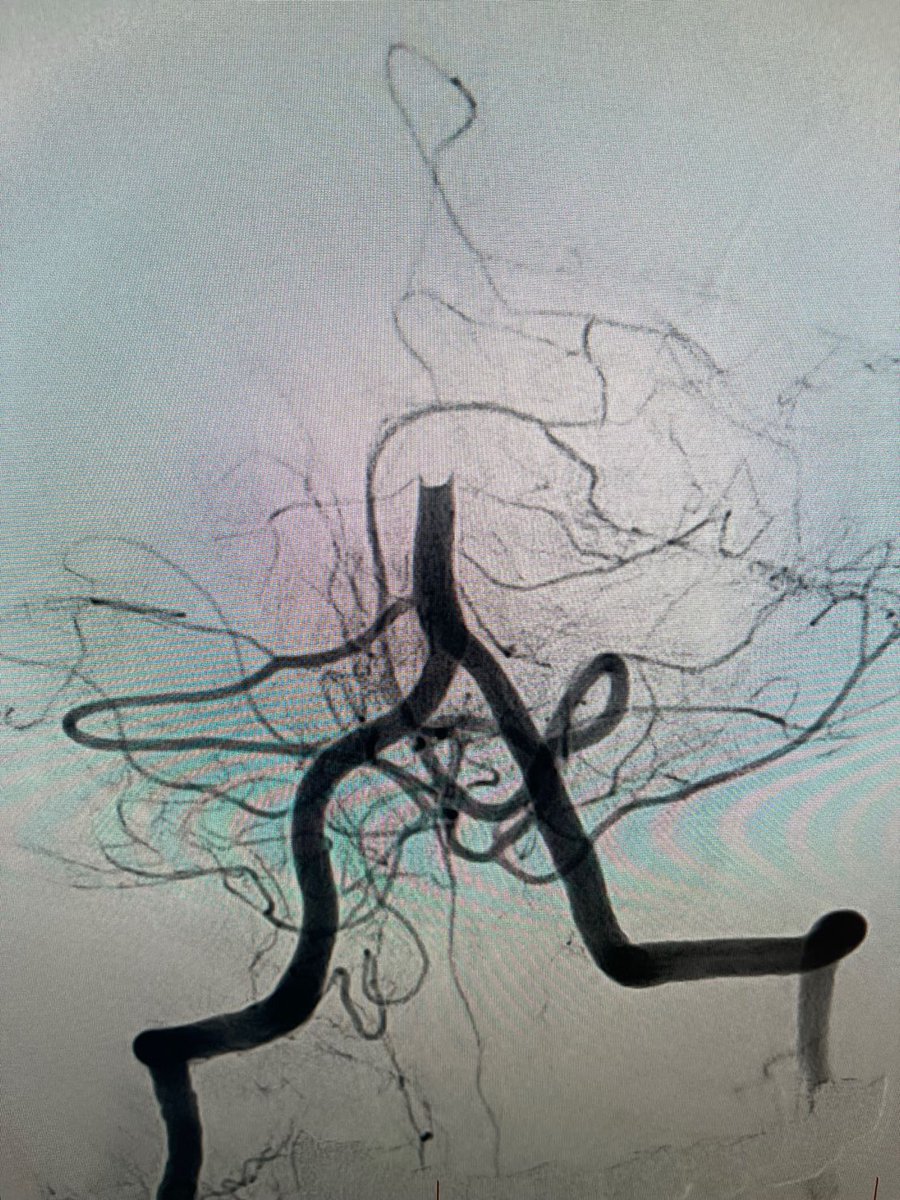

US HCPs: Radial access with #BMX81 through a tortuous arch to deliver #RED62 & #RED43 for acute basilar occlusion. First Pass recanalization. Courtesy of Dr. Agrawal in Las Vegas. Rx only. For risk info: bit.ly/2BYj7Yj Clinical results may vary

PenNeuro's tweet image. US HCPs: Radial access with #BMX81 through a tortuous arch to deliver #RED62 & #RED43 for acute basilar occlusion. First Pass recanalization. Courtesy of Dr. Agrawal in Las Vegas. Rx only. For risk info: bit.ly/2BYj7Yj Clinical results may vary